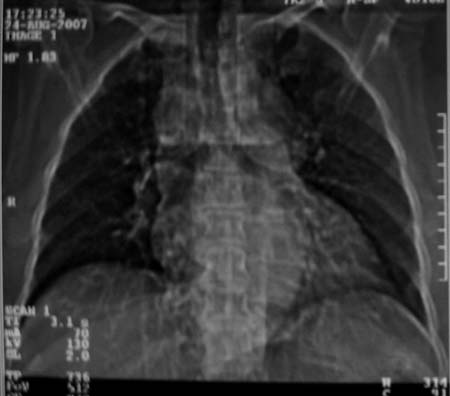

以下是引用zjzjr在2007-8-30 22:22:00的发言:[br]右上肺肺囊肿合并感染.右下肺肺大泡.左肺舌段感染.